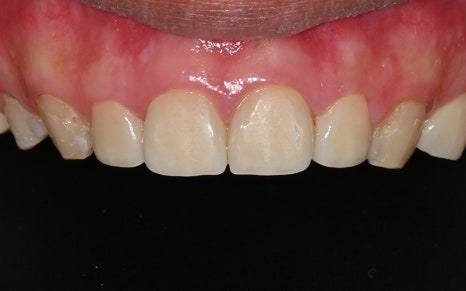

This is what it looked like after some of the treatment had been completed.

The most noticeable change was,

above all, the aesthetic restoration of the front teeth.

Looking at the before-treatment photos,

the front teeth had large cavities and damage

to the point that it was hard to smile,

and the areas filled with resin here and there

were also a major source of aesthetic stress.

But the post-treatment photos

feel like a completely different person.

As if the teeth had originally been pretty and straight,

the color looks natural,

and the shape was restored to fit the face perfectly.

In fact, the patient said,

“This really feels like my original tooth,

and it doesn’t look like I had any treatment at all,” and expressed satisfaction.